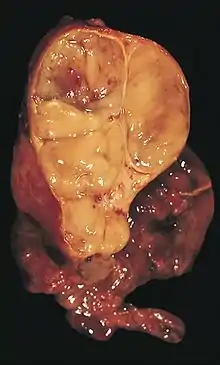

| An encapsulated thymoma (mixed lymphocytic and epithelial type) | |